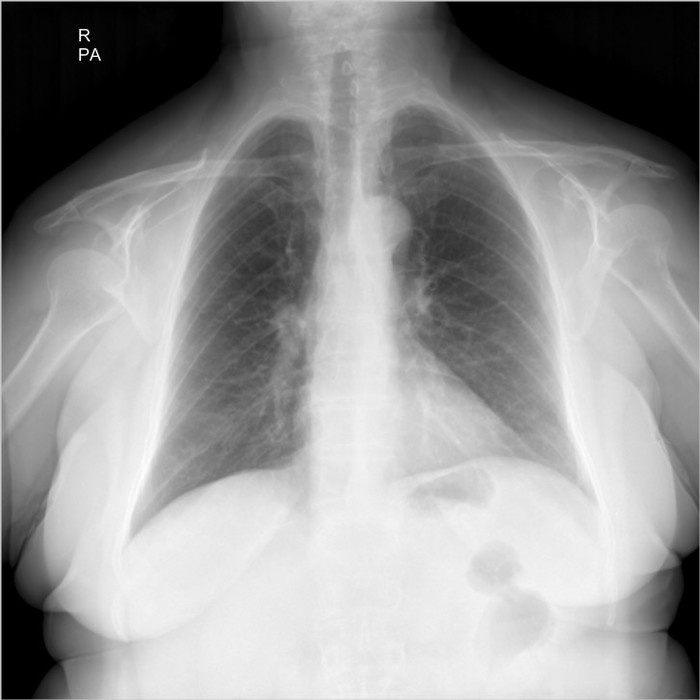

Здравствуйте, я работаю лаборантом в рентген кабинете, в госпитале, в Ливий. К сожалению у нас нет рентгенолога, и в некоторый случаях мне приходиться "читать" снимки самому... Со мной вместе работает мама, она медсестра в реанимаций. Ей сейчас 67 лет, решил сделать ей рентген лёгких, на боли в груди она не жалуется. Я начал изучать снимок и увидел образование в форме круга в левом легком возле бронха, подскажите мне пожалуйста что это такое и стоит ли мне беспокоится. Фото в негативе и позитиве прилагаю ниже.